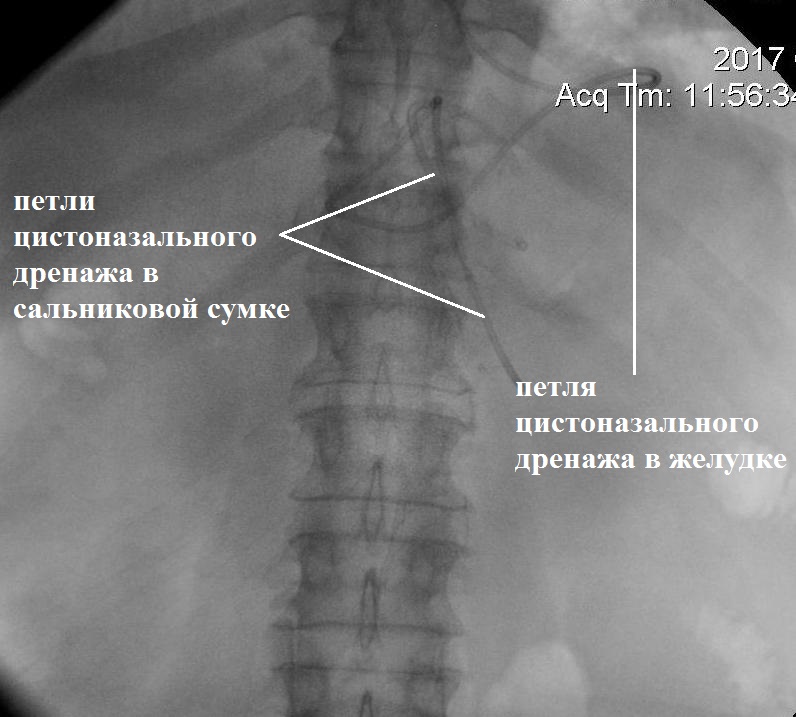

Под контролем эндосонографии 04.10.2017 г. выполнено эндоскопическое цистоназальное трансгастральное дренирование ОЖС сальниковой сумки с установкой цистоназального дренажа диаметром 5 Fr и цистогастрального дренажа типа double PigTail диаметром 7 Fr (рис. 3).

Рис. 3. Этапы цистоназального дренирования жидкостного скопления сальниковой сумки (13-е сут болезни). А — эндосонограмма жидкостного скопления сальниковой сумки

Рис. 3. Этапы цистоназального дренирования жидкостного скопления сальниковой сумки (13-е сут болезни). Б — цистоназальный дренаж в полости сальниковой сумки

Рис. 3. Этапы цистоназального дренирования жидкостного скопления сальниковой сумки (13-е сут болезни). В — интраоперационная фистулография

Получено 200 мл жидкости бурого цвета, уровень амилазы в которой составил 16 000 Ед/л. При бактериологическом исследовании отделяемого роста микроорганизмов не выявлено.